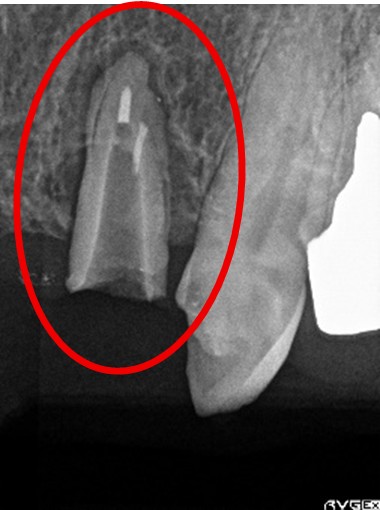

ブリッジの支台になっていた2本のうち1本が保存不能のため抜歯しました。抜歯後3本欠損のところにスマートデンチャーをいれました。

前歯2本欠損のところに固定制のブリッジが入っていましたが、1本の支台歯は歯根のまわりの骨がほとんどなくなっていましたので、保存することができませんでした。抜歯後3本欠損のところを補う方法は、部分入れ歯、再度ブリッジ、インプラントがあります。この症例の場合、ブリッジは早期に支台になる歯がダメになる可能性が高かったので、再度ブリッジはお勧めしませんでした。患者さんは、部分入れ歯のうちの金属のバネがないスマートデンチャーを選択されました。

赤丸は抜歯しました